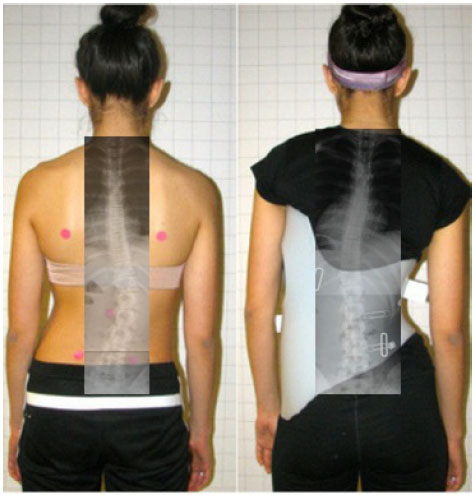

هل تختلف نتائج العلاج بالحزام بين المرضى؟

نعم، هناك عدة عوامل تؤثر على نجاح العلاج باستخدام الحزام، من أبرزها:

الجنس: الفتيات أكثر استجابة للعلاج بالحزام من الذكور، بسبب مرونة العمود الفقري وفترة العلاج الأقصر.

الوزن: المرضى الذين يعانون من زيادة الوزن يواجهون صعوبات في العلاج بسبب انخفاض قدرة الحزام على التأثير عبر الأنسجة.

الالتزام: النجاح يعتمد بشكل كبير على مدى التزام المريض بارتداء الحزام طوال اليوم.

- المتابعة المنتظمة: من الضروري إجراء فحوصات دورية لتقييم تقدم العلاج وتعديل الحزام إذا لزم الأمر.

- الالتزام بارتداء الحزام: يجب ارتداء الحزام وفقًا لتعليمات الطبيب لتحقيق أفضل النتائج.

- التواصل مع الفريق الطبي: لا تتردد في طرح أي أسئلة أو مخاوف على الفريق الطبي المعالج.

من خلال فهم العوامل المؤثرة على فعالية العلاج بالحزام، يمكن للمرضى وأولياء الأمور اتخاذ قرارات مستنيرة بشأن إدارة اعوجاج العمود الفقري مجهول السبب وتحقيق أفضل النتائج الممكنة.